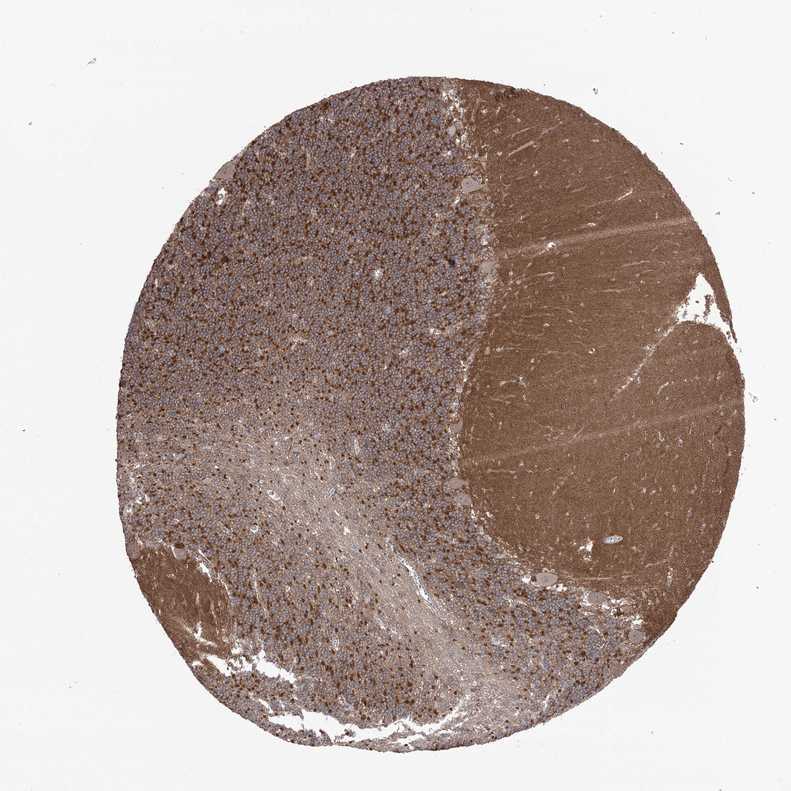

CEREBELLUM - Antibody stainingi

Antibody staining in the annotated cell types in the current human tissue is reported as not detected, low, medium, or high, based on conventional immunohistochemistry profiling in selected tissues. This score is based on the combination of the staining intensity and fraction of stained cells.

Each image is clickable and will lead to virtual microscopy that enables deeper exploration of all samples and also displays staining intensity scores, fraction scores and subcellular localization as well as patient and tissue information for each sample.

Antibody HPA037863

Purkinje cells Low

Cells in granular layer High

Cells in molecular layer Low